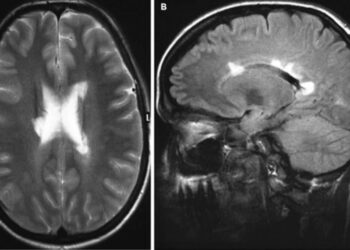

X-связанная адренолейкодистрофия (X-ALD) - редкое наследственное нарушение обмена веществ, при котором накопление жирных кислот с очень длинной цепью (VLCFAs) приводит...